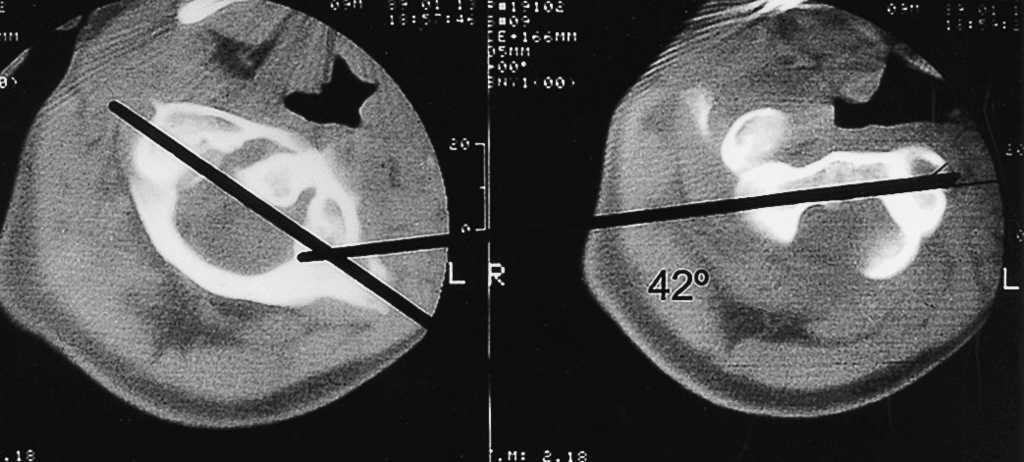

Niño de 7 años de edad con historia de tortícolis fija de 17 semanas de evolución a raíz de una infección respiratoria superior; antes de ser remitido, fue tratado mediante antiinflamatorios no esteroideos (AINE), ortesis cervical tipo Schanz y tracción elástica seguida de ortesis cervical sin resultado positivo. Mediante TAC se diagnosticó de SRCAA ipo I con una divergencia de 25° (fig. 4) y se inició un tratamiento con tracción hasta llegar a 8 kg, a las 3 semanas presentó unas rotaciones simétricas y la TAC (fig. 5) mostró una reducción completa, por lo que se inmovilizó mediante halo-yeso que se mantuvo 6 semanas, continuándose el tratamiento 6 semanas más con ortesis cervical blanda. Ocho años después, la función es normal, no presentando secuelas.

Figura 4. Tomografía axial computarizada donde se puede apreciar la deformidad rotacional del complejo C1-C2 en el segundo paciente con angulación de 25°.

Figura 5. Reconstrucción de la tomografía axial computarizada de control 3 semanas después, donde se aprecia la simetría entre la apófisis odontoides y las masas laterales del atlas con corrección completa de la rotación.